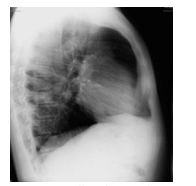

A radiografia é o método mais comum de diagnóstico por imagem na atualidade. Para que esse exame possa proporcionar boas imagens diagnósticas, é necessário respeitar incidências específicas em determinados segmentos do corpo que será radiografado. A imagem a seguir mostra uma radiografia de tórax, cuja a incidência utilizada foi

Fonte: https://www.researchgate.net/figure/Radiografia-de-torax-perfil-revelahipotransparencia-do-lobo-inferior-desse-lado-como_fig11_260010003. Acesso em: 15 set. 2022.